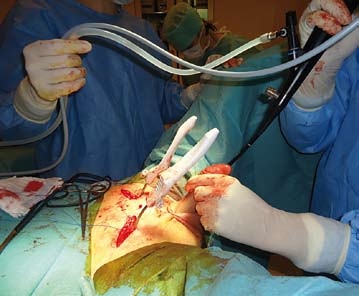

Na perineu provedeme střední řez a uvolníme bulbus uretry od okolních tkání. Následují dvě krátké suprapubické incize, ze kterých se na každé straně uvolní podkoží letálně od tuberculum publicum až na Cooperovy vazy. Poté jsou z perinea zavedeny retropubickou cestou protahovací jehly a jimi vytaženy oba vrapované silikonové závěsy slingu. Následuje kontrola neporušenosti stěny měchýře a uretry, kterou provedeme pomocí peroperační cystoskopie flexibilním cystoskopem. Na vrapované závěsy navlečeme dotahovací kroužky. Do penilní uretry je zaveden jednorázový katetr CH 16, na který je napojen infuzní set s fyziologickým roztokem. Sling je dotahován za kontroly irigace uretry gravitačním tlakem 39 cm fyziologickým roztokem až do zástavy kapání. Tato část se pro kontrolu opakuje třikrát. Nakonec zavedeme balónkový katetr Tieman CH 16-18. Poté implantát před uzavřením obložíme houbičkou Garamycinu, která slouží jako nosič antibiotika. Následuje sutura ran vstřebatelným šicím materiálem. Po celou dobu proplachujeme gentamycinem zředěným fyziologickým roztokem.